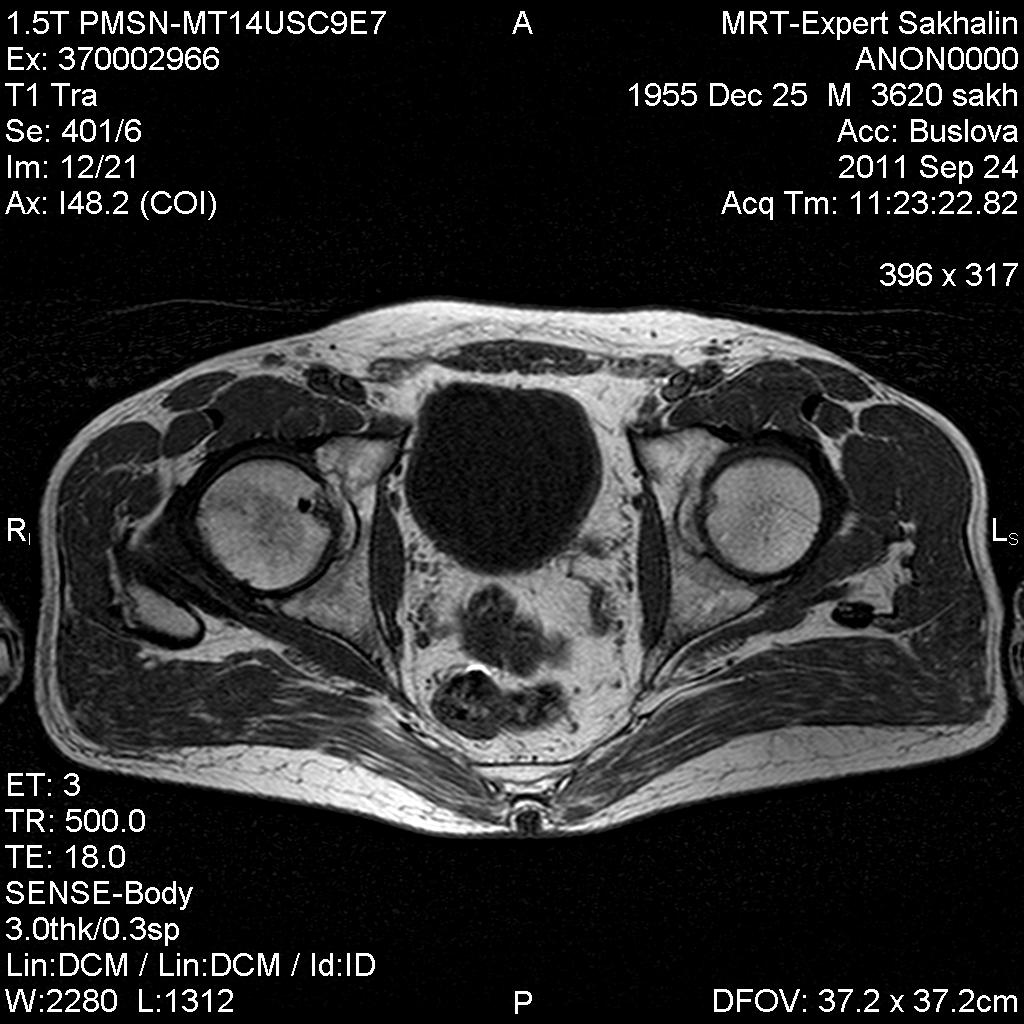

Мужчина пришел на МР-исследование правого тазобедренного сустава.Рентгенограммы также принес( удивительно- скорее,исключение,чем норма). Пока выставляю рентенограммы завтра МР-картинки.

У мужчины уже лет 5 назад были выявлены склеротические очаги в подвздошной и бедренных костях, тогда же подозревали бластические метастазы, но обследования показали норму ( судя по записям в амбулаторной карте).

А вот про очаг в шейке данных не было.

Добавила МР-картинки.

В подвздошной кости фокус аинтенсивный , без перифокальной реакции, учитывая сигнальные характеристики  и отсутствие  динамики -бесструктурный очаг обезыствления.В голове бедренной кости очаг с характеристиками жидкостного характера, четким, неровным контуром, без перифокального отека- кистовидая перестройка ?

Irena пишет о головке правого бедра? То, что в шейке бедра не киста разве?  А слева нормальная головка?

Слева ничего особенного в головке не вижу.

В головках, подвздошных костях  есть мелкие  склеротические очажки, участки жировой дистрофии.В шейке скорее всего,киста, конечно.